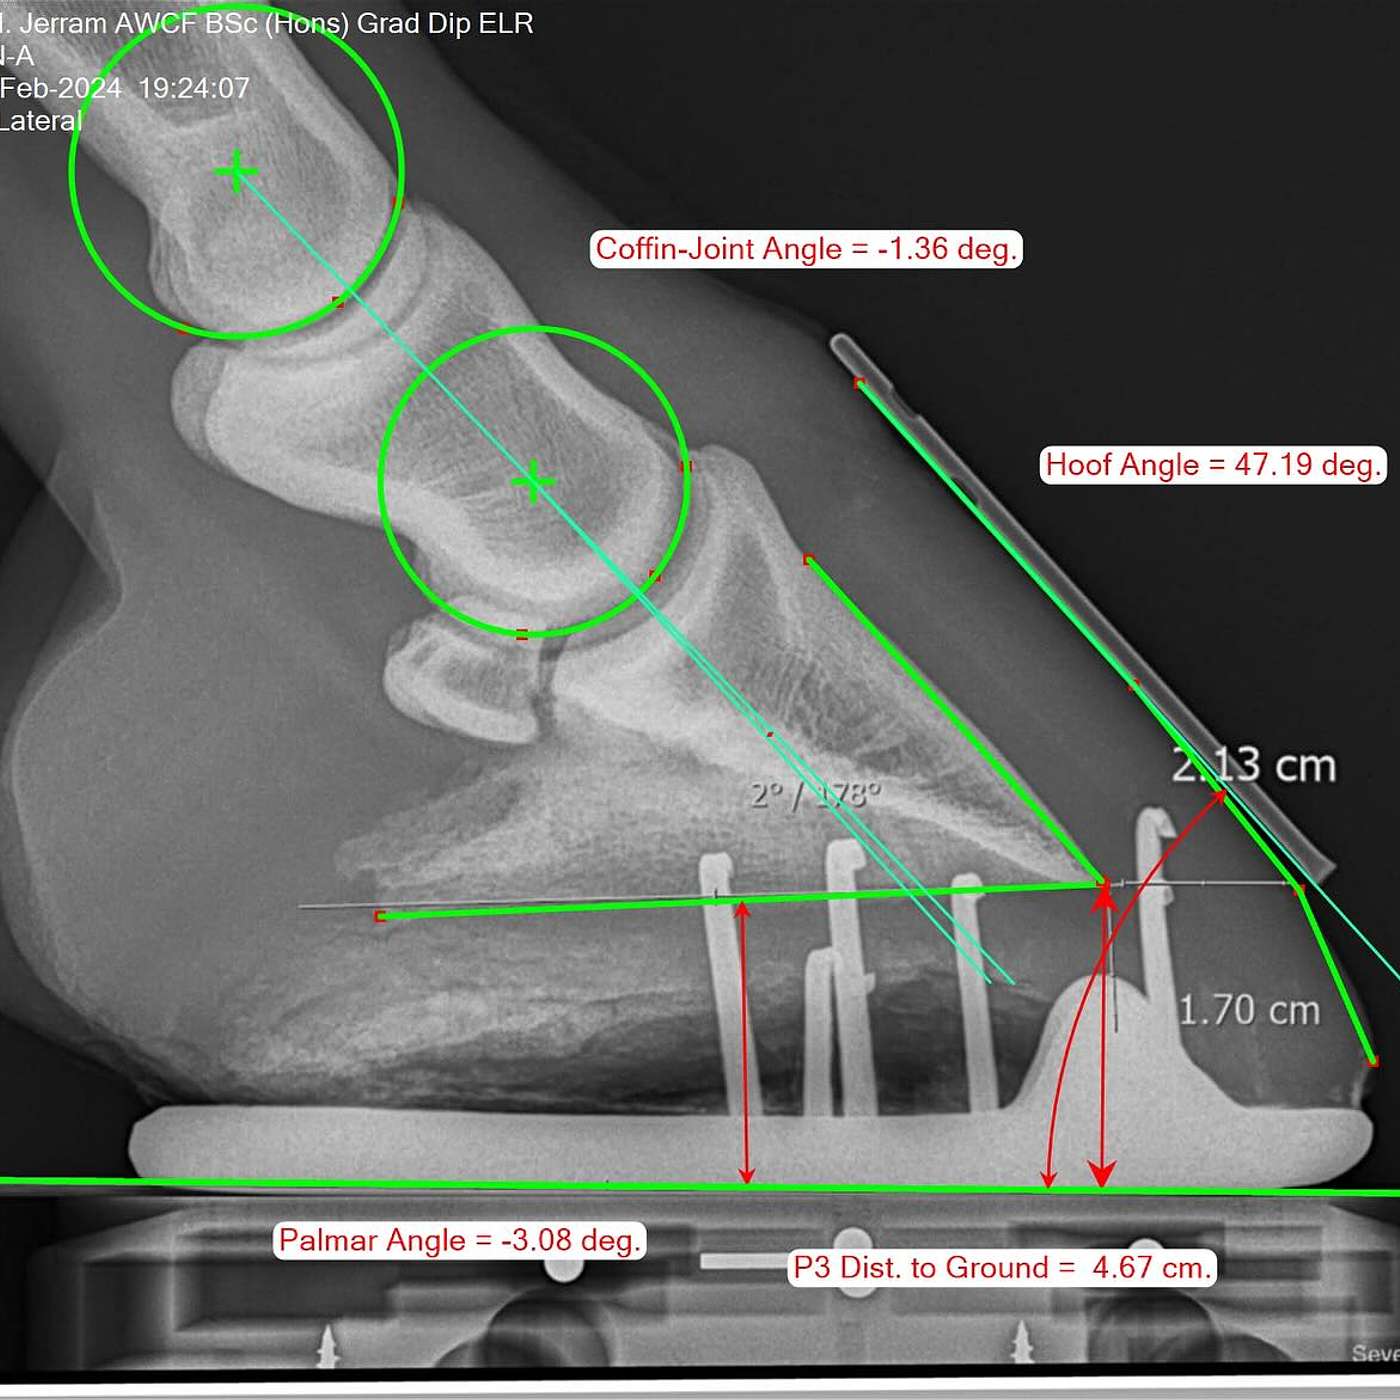

In this episode of The Hoofcare Companion, we dive into the critical role of radiography in assessing equine foot balance. Traditionally, farriers and veterinarians relied on visual and tactile assessment to guide trimming and shoeing, but modern diagnostic imaging has transformed hoof care. Join host Marc Jerram as we explore how radiographs provide deeper insights into hoof alignment, pastern axis, palmar angles, sole depth, and mediolateral balance. We discuss how these measurements influe...